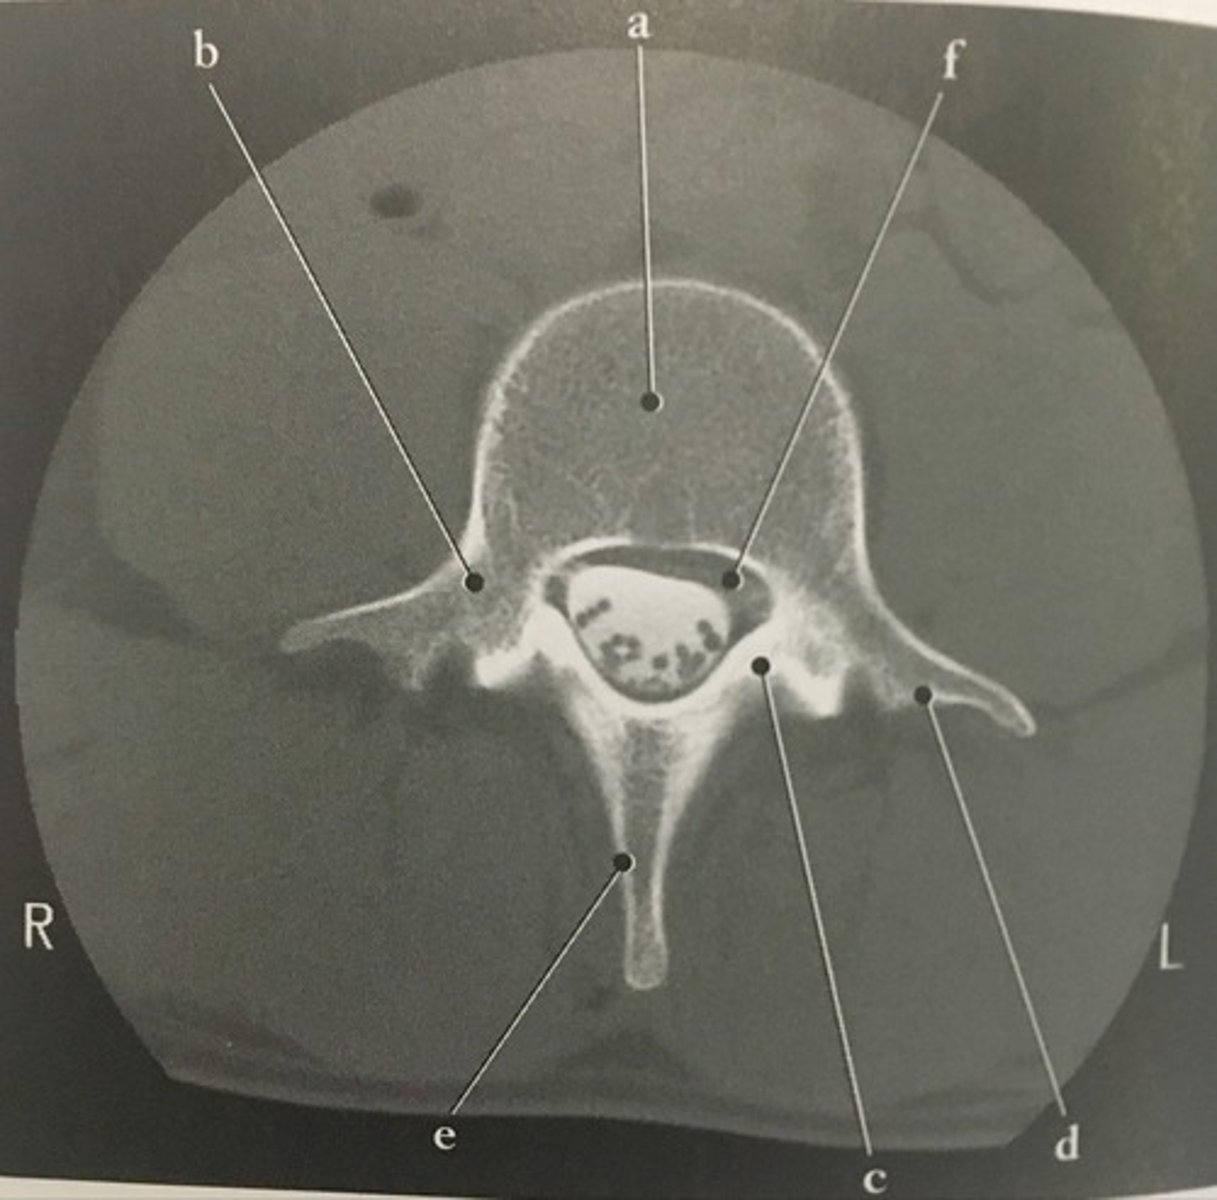

Identify structure A on this axial CT slice of the lumbar vertebra.

93

Pedicle

<p>Identify structure B on this axial CT slice of the lumbar vertebra.</p>

New cards

Identify structure C on this axial CT slice of the lumbar vertebra.

95

Transverse process

<p>Identify structure D on this axial CT slice of the lumbar vertebra.</p>

Identify structure E on this axial CT slice of the lumbar vertebra.

97

Vertebral foramen

<p>Identify structure F on this axial CT slice of the lumbar vertebra.</p>